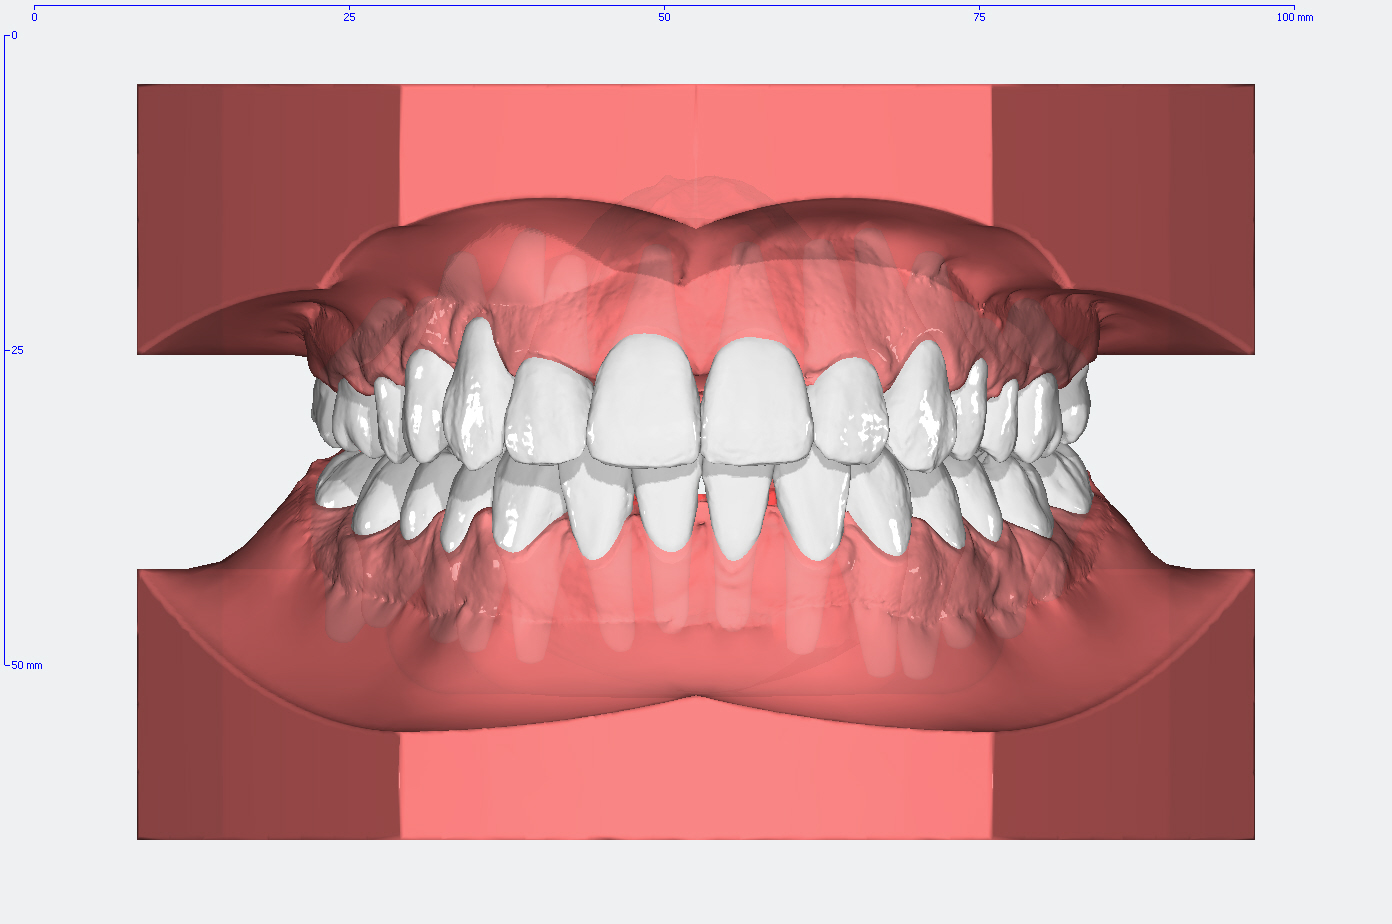

Die Entwicklung der Zahnstellung im Gebiß anhand von 3D Modellen

In den Abbildungen unten sehen Sie den Vergleich der Zahnstellung in den Gebissmodellen in der ursprünglichen Form und nach der kieferorthopädischen Behandlung.